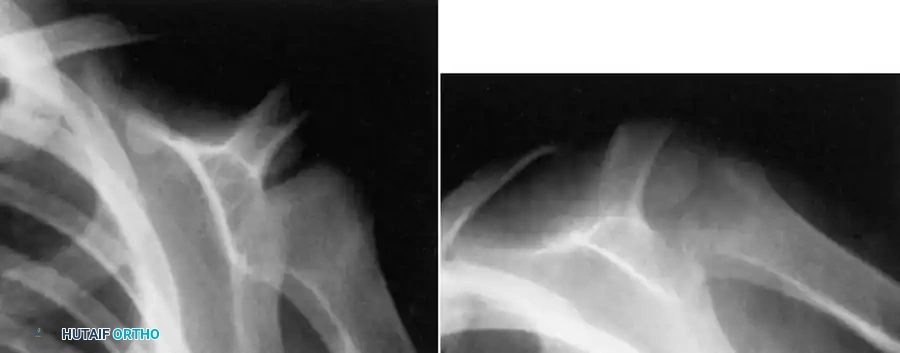

Fig. 16-7 Subacute osteomyelitis of proximal humerus. Note the localized radiolucency and surrounding sclerosis, which can easily be mistaken for a benign bone cyst or a primary bone neoplasm.

Differentiating these infectious lesions from primary bone tumors can be exceedingly difficult based on plain radiographs alone. While there are no massive series reporting Magnetic Resonance Imaging (MRI) findings exclusively in subacute osteomyelitis, MRI is invaluable. Hempfing et al. demonstrated that MRI is critical not only for diagnosing the condition by identifying bone marrow edema, soft tissue extension, and the "penumbra sign" (a rim of vascularized granulation tissue lining the abscess cavity), but also for precise preoperative planning of the surgical approach.